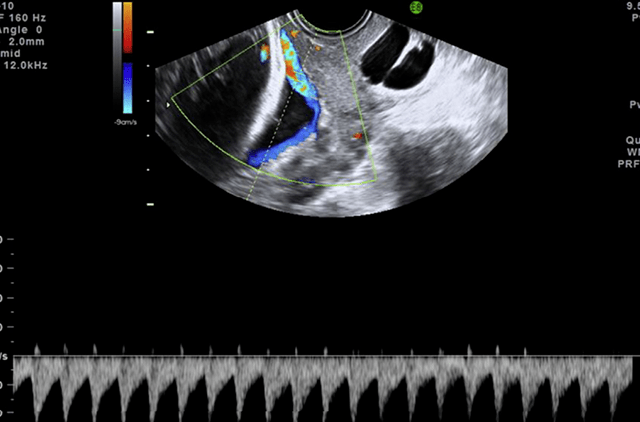

前置血管的超声诊断标准包括:(1)脐血管无华通胶保护,且位于宫颈内口

图片尺寸640x504